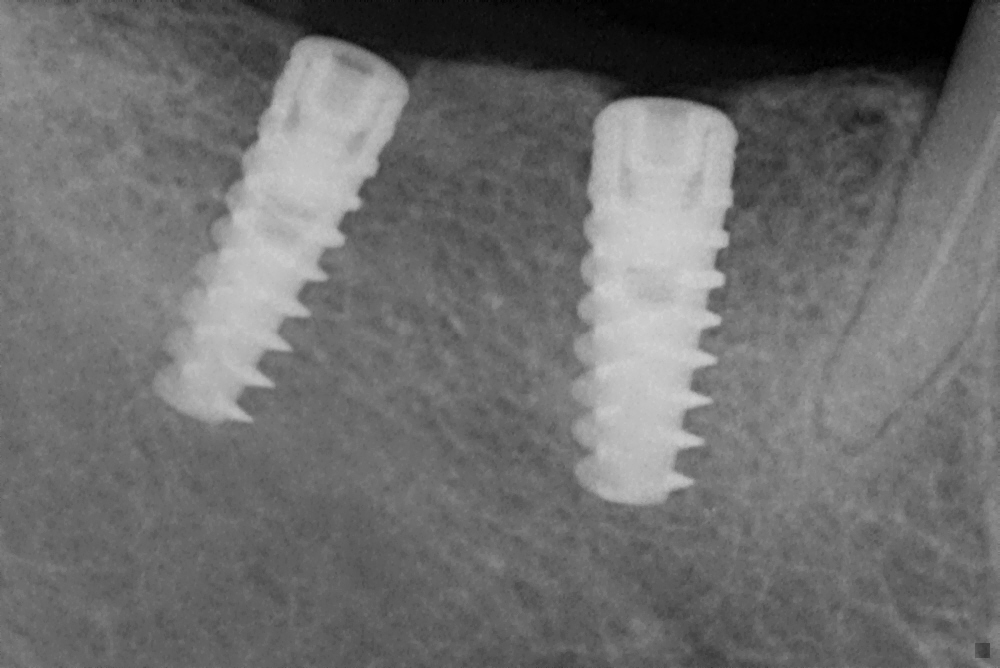

Enter Malhar Dental Clinic, a beacon of hope for those facing dental dilemmas. Known for its state-of-the-art facilities and compassionate care, the clinic offers a range of services, with dental implants being one of its specialties. Dental implants are not just a cosmetic solution; they provide a practical and durable alternative to dentures or bridges. They are designed to blend seamlessly with natural teeth, providing stability and comfort that can last a lifetime.

Dr. Priya explained the procedure in detail, addressing Rohan’s concerns and ensuring he felt comfortable with each step. The dental implant process at Malhar Dental Clinic is meticulously planned, beginning with a comprehensive evaluation and ending with a perfectly crafted smile. Advanced technology ensures precision in implant placement, while the clinic’s focus on patient comfort makes the experience as smooth as possible.